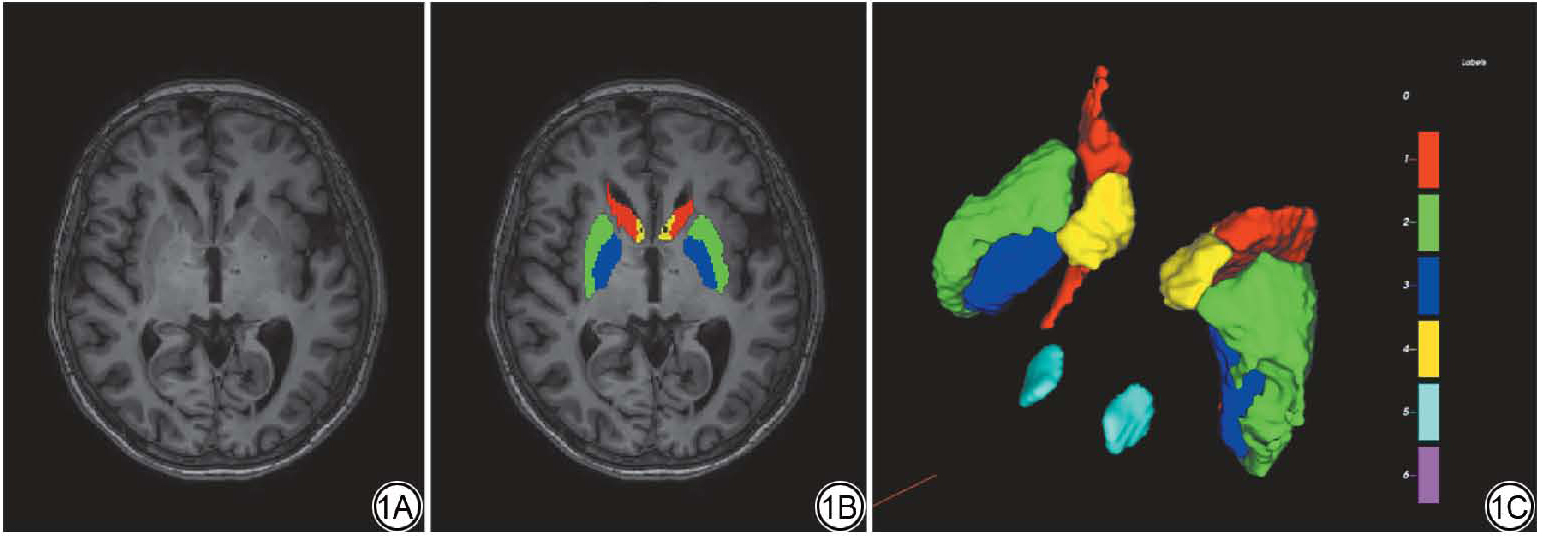

图1  患者勾画示意图。1A:T1 原始图像断层截图;1B:原始图像的标注截图;1C:标注后的3D渲染图。

Fig. 1  Schematic diagram of patient segmentation. 1A shows an axial section of the original T1-weighted image; 1B displays the annotated version of the original image; 1C presents the corresponding 3D rendering after annotation.